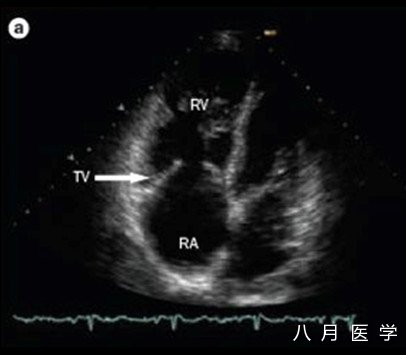

房颤的病因包括甲亢、贫血、感染、缺血性心脏病、瓣膜病、药物中毒或使用兴奋剂。

图8